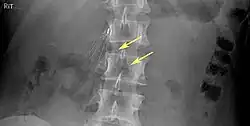

Of these IVC filter side effects, 328 involved device migration, 146 involved embolizations after detachment of device components, 70 involved perforation of the IVC, and 56 involved filter fracture. Much of the medical community believes that this large number of adverse events is related to the heart filter remaining in place for longer than necessary.

- Filter fracture

- 9% (12 of 132 patients) delayed filter penetration of the IVC greater than 3 mm

- Parts of filter broke off in 2% (5 of 230 patients)

- Filter fracture: Broken struts migrate to retroperitoneum, requiring exploration.[21] Also struts can migrate to the heart and can cause pericardial effusion and tamponade.[22]